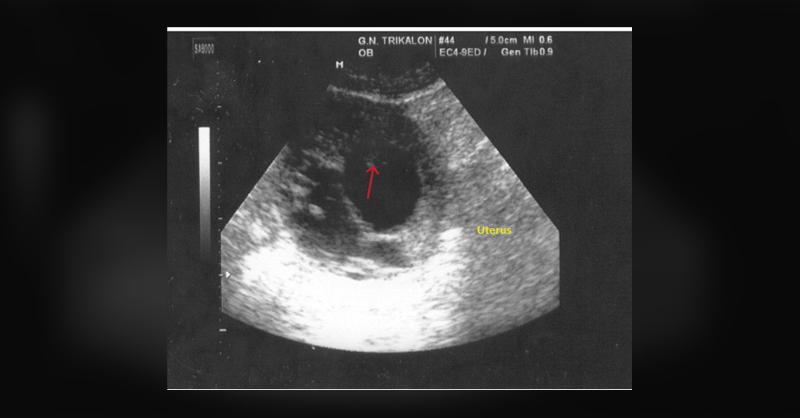

- Unraveling the Cause of Severe Vaginal Bleeding in a Patient with a Positive Pregnancy Test

A 27-year-old woman, with a history of three vaginal deliveries and pelvic inflammatory disease, presented with severe vaginal bleeding. Despite never using an intrauterine contraceptive coil, she had a history of recurrent hospitalizations for pelvic inflammatory disease three years ago. She complained of mild lower abdominal discomfort persisting

Unraveling the Cause of Severe Vaginal Bleeding in a Patient with a Positive Pregnancy Test